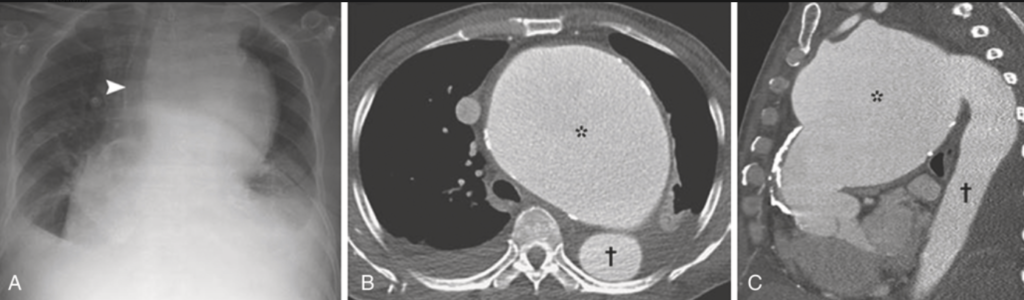

① 近位大動脈の拡張、上行大動脈の前外側壁の線状石灰化(古典的なXp所見)

動脈瘤は50%は上行大動脈弓に生じ、巨大化しても症状に乏しいため”aneurysm of sings”と呼ばれる。ついで30-40%は横行弓に生じ、縦隔内の構造物に隣接するため”aneurysm of symptoms”と呼ばれる。